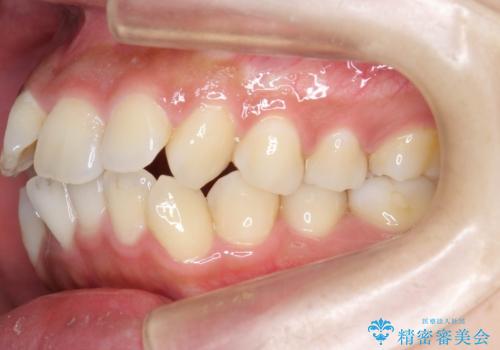

ガタつきと口元の改善 抜歯を伴うワイヤー矯正

- 唇の閉じづらさと、前歯のがたつきの改善を希望され来院されました。

抜歯を行わなくてもなんとか並べられる歯並びですが、唇の閉じづらさをしっかりと改善するため抜歯を伴うマルチブラケット矯正を行うこととしました。

前歯をしっかりと後方に引いたことで、唇は閉じやすくなり、仕上がりに満足いただくことができました。